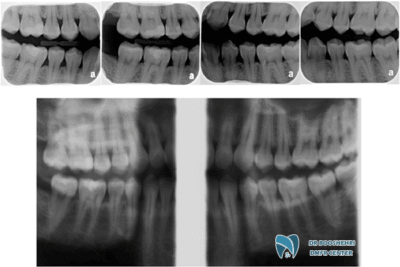

Jawbone radiography, especially in the form of bitewing radiography, is one of the most precise and advanced dental imaging methods widely used to Evaluation of jawbone health and teeth. This method enables dentists to obtain clear and accurate images of the areas between the teeth and the jawbones. It is particularly effective for diagnosing bone loss, gum diseases, and damage caused by decay in the posterior areas of the jaw.

In this method, the patient holds a small plate known as a “bitewing” between their teeth to ensure proper image capture. These two-dimensional images help the dentist identify changes in the jawbone. The use of jawbone radiography allows practitioners to detect potential issues before they develop into more serious problems and to take timely therapeutic actions.

In research conducted by scientists, the accuracy of two methods of bitewing radiography—extraoral and intraoral—was examined for detecting interproximal caries and assessing jawbone health. The results indicated that both methods perform similarly in diagnosing proximal surface caries. However, when it comes to opening posterior interproximal contacts, intraoral bitewing is more accurate (95.9%) than extraoral bitewing (81.7%). Additionally, extraoral bitewing outperformed standard panoramic images (48.5%) in opening interproximal contacts. These findings assist patients in choosing the best radiographic method based on their diagnostic needs, especially when evaluating jawbone health.

Jawbone radiography allows dentists to accurately assess jawbone conditions without the need for invasive methods. These two-dimensional images help practitioners observe changes in bone density and thickness, which may indicate serious issues such as bone resorption or periodontal diseases. One of the standout features of this method is its ability to visualize interproximal areas that are often missed by other techniques. Decay and bone changes in these regions are not easily detectable, potentially leading to more serious problems like dental and gum infections. Jawbone radiography enables dentists to identify these issues in a timely manner.

Bitewing radiography effectively displays bone changes that may result from bone resorption or gum diseases. When the jawbones undergo resorption due to disease or continuous pressure, their structure changes in bitewing images. By observing a reduction in the height or density of the bone, dentists can diagnose bone resorption. This is especially important for patients in the early stages of periodontal disease, as bitewing radiography can identify early signs of bone loss before conditions worsen. These images help practitioners to implement necessary treatments in a timely manner.